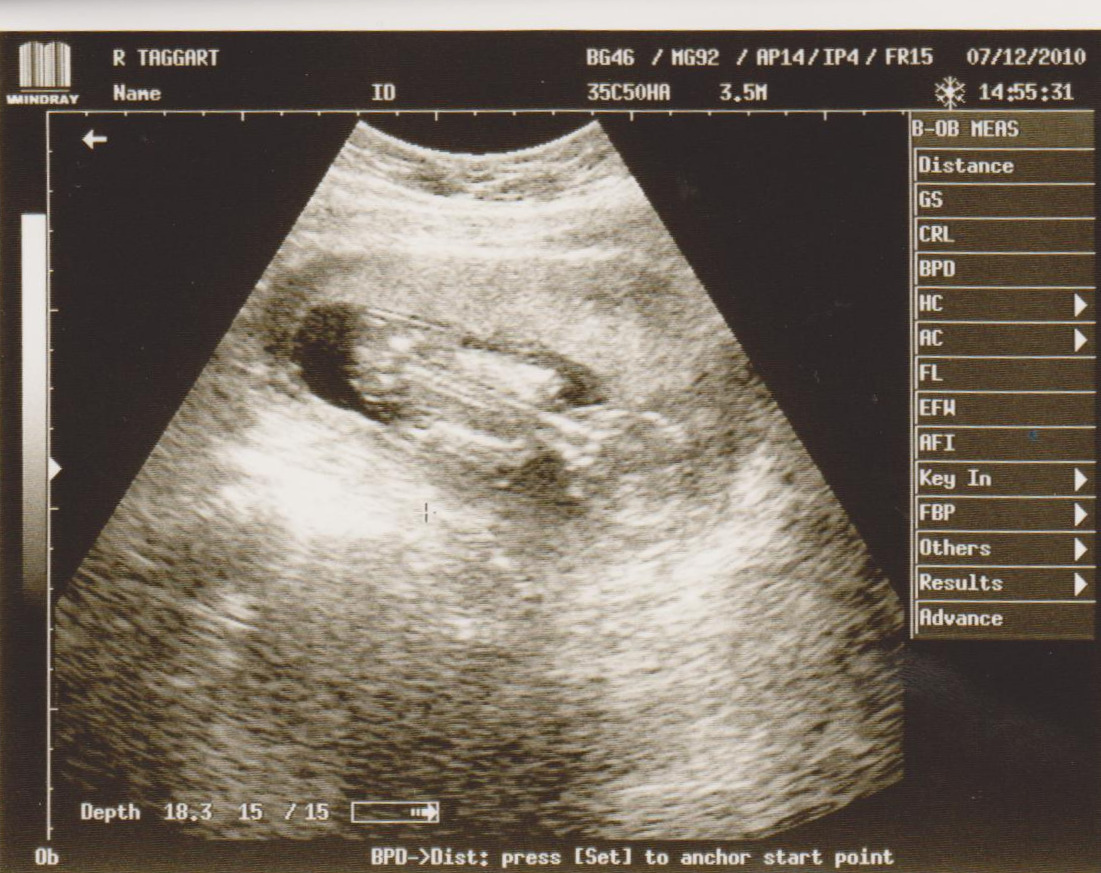

Here is Peanuts back, spine and booty =)